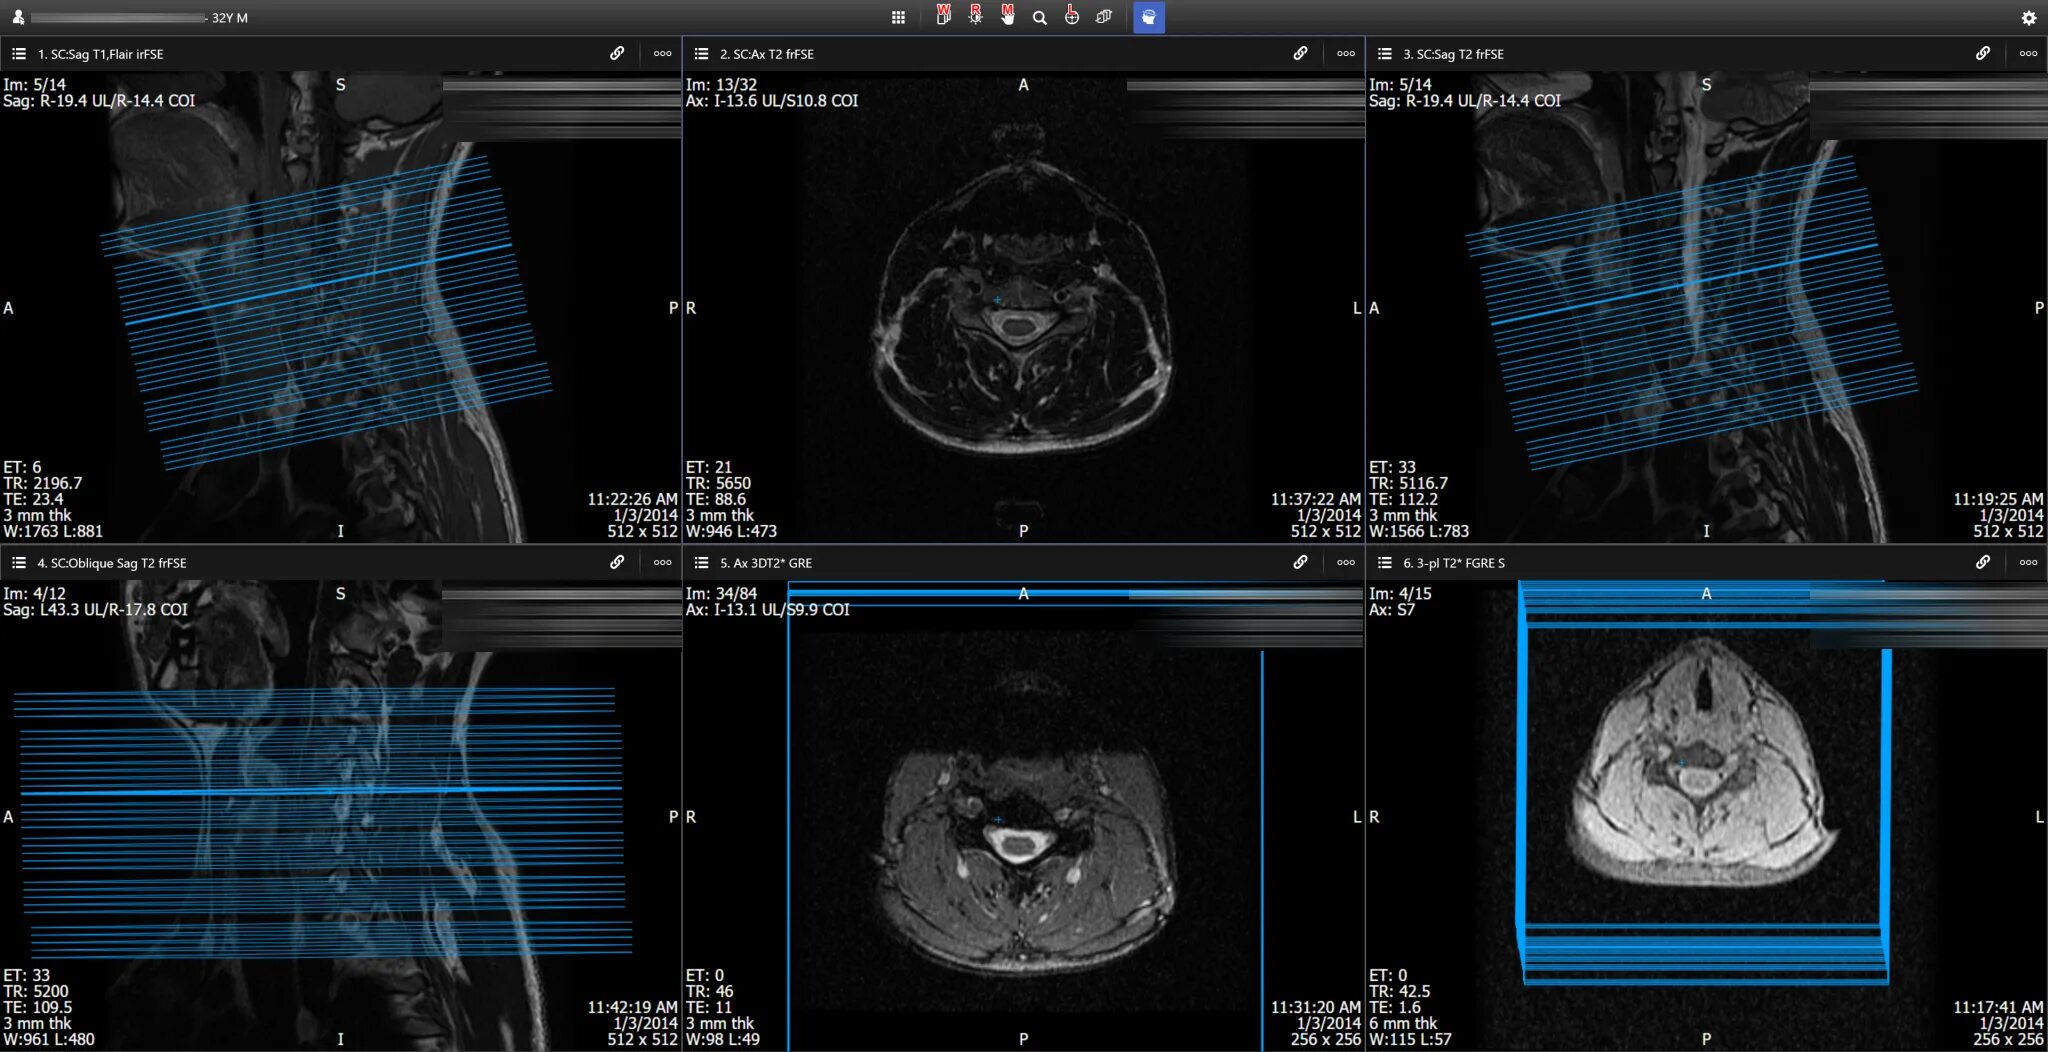

Dicomdir чем открыть снимки мрт